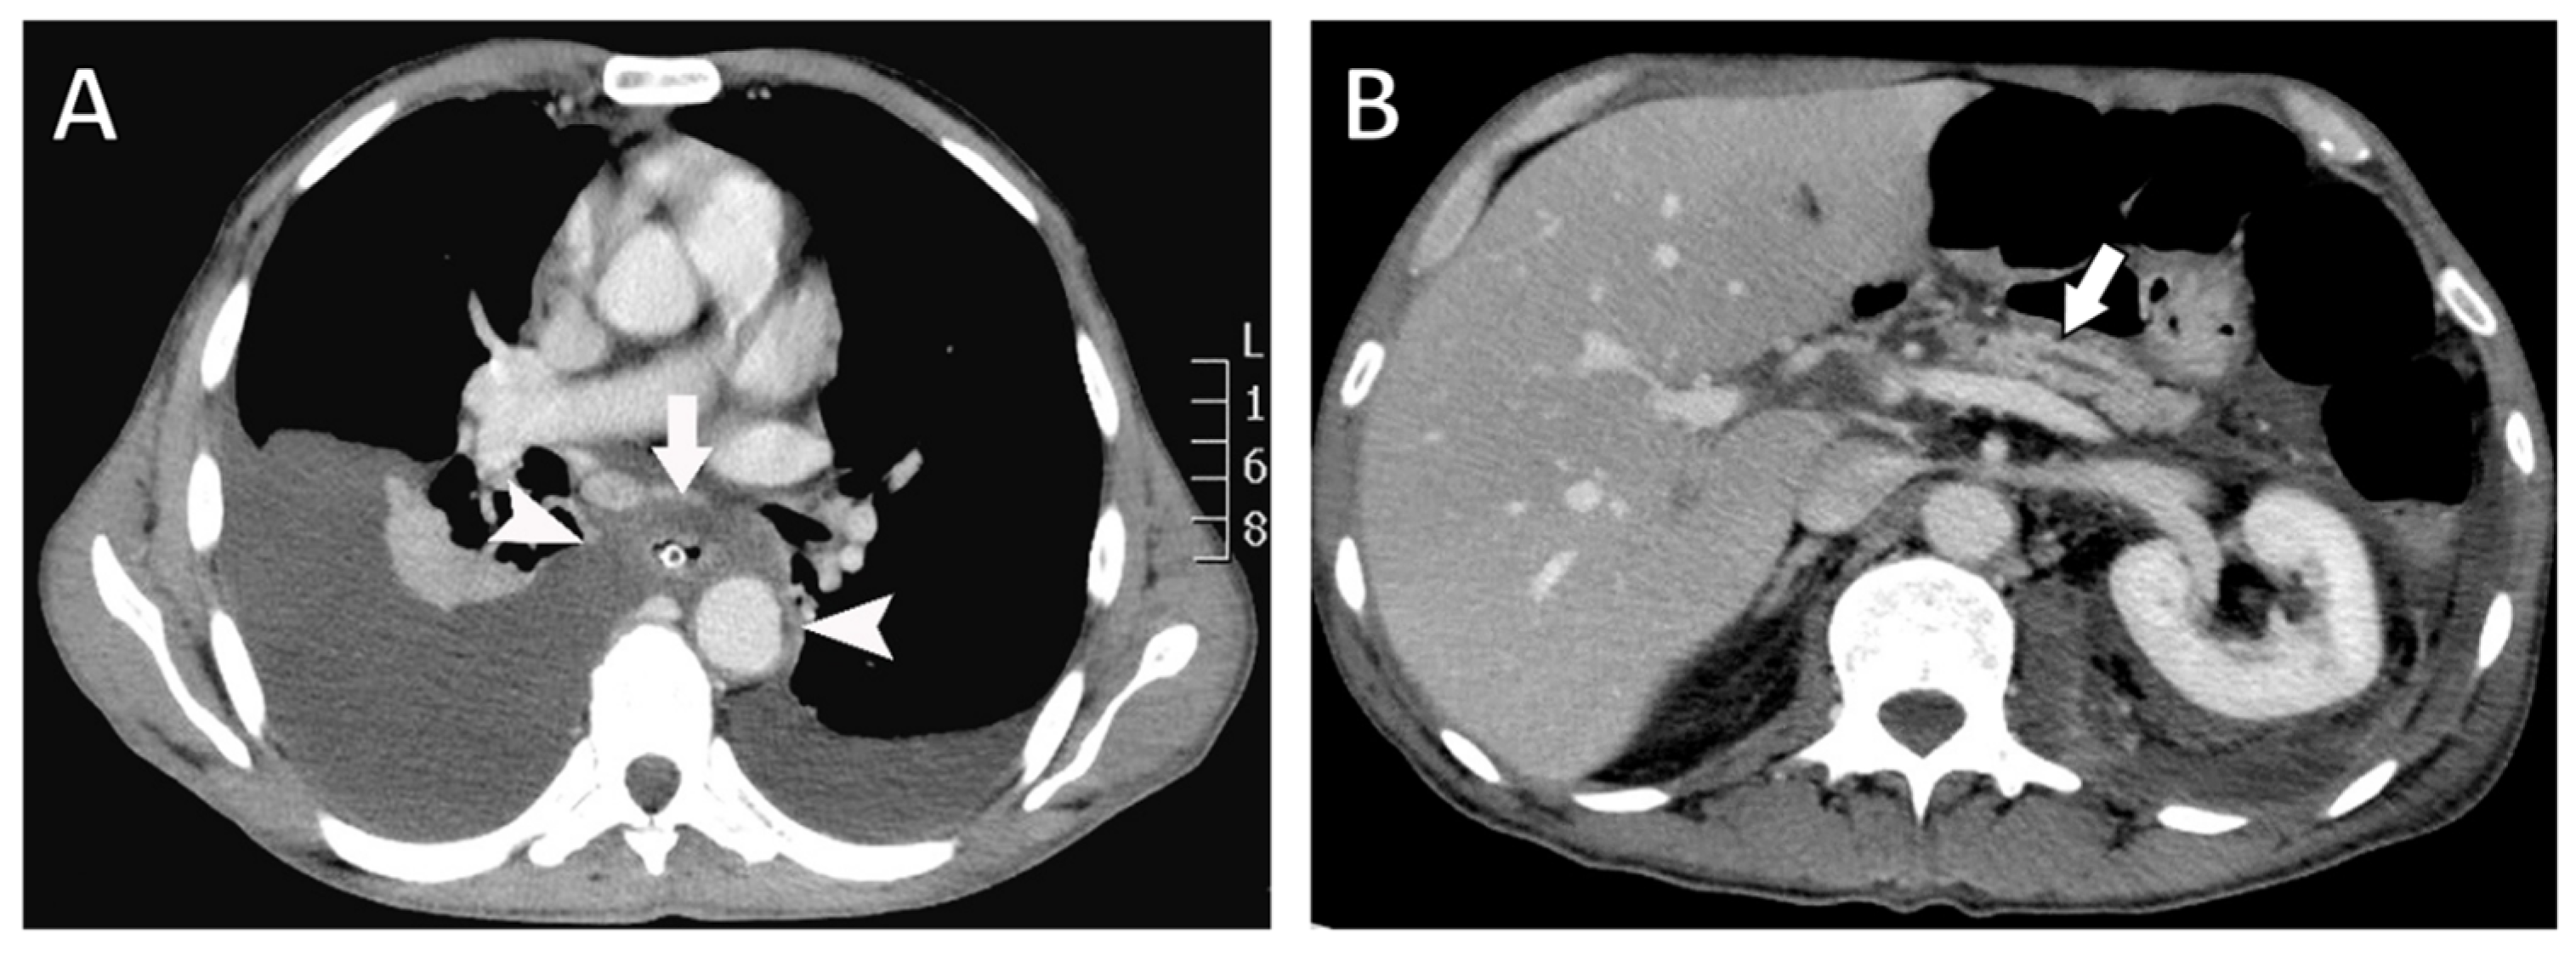

Chest radiography revealed bilateral pleural effusions, more pronounced on the right side (Figure 1). Contrast-enhanced thoracoabdominal computed tomography (CT) confirmed bilateral pleural effusions with associated ascites (Figure 2). The pancreas appeared atrophic with dilatation of the main pancreatic duct, consistent with chronic pancreatitis. A peripancreatic fluid collection extended toward the esophageal hiatus, coursing into the mediastinum and pleural spaces. Magnetic resonance imaging (MRI) confirmed pancreatic atrophy, while magnetic resonance cholangiopancreatography demonstrated an irregularly dilated main pancreatic duct measuring approximately 1 cm with intraductal filling defects. A fistulous tract originating from the pancreatic body and extending through the left side of the esophageal hiatus into the mediastinum was identified. The biliary tree and gallbladder were unremarkable, and no further pancreatic lesions were appreciated (Figure 3), thus not necessitating further evaluation with EUS. These findings established the diagnosis of chronic calculous pancreatitis complicated by a pancreaticopleural fistula. As imaging studies took place promptly following initial presentation, and the suspicion of pancreaticopleural fistula was established early, pleural fluid amylase levels were not sent for this patient.

Figure 2.

Contrast-enhanced computed tomography (CT) findings. (A) Axial CT image showing a fluid collection surrounding the esophagus (arrow) extending through the mediastinum and communicating with both pleural cavities (arrowheads). A nasogastric tube is visualized within the esophageal lumen. (B) Axial CT image demonstrating pancreatic atrophy with dilatation of the main pancreatic duct (arrow).